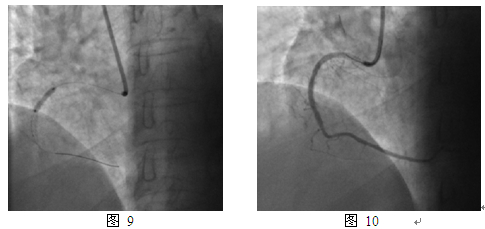

2012年3月发作活动时胸痛,休息可缓解,第一次住我院。入院查体无特殊阳性发现。超声心动图:静息状态下心内结构功能未见异常,LVEF 65%。冠脉造影:右冠支架内再狭窄80%(图8)。同期介入治疗,球囊Fire Star 2.5mm x 15mm预扩,最大14atm,PEB球囊Sequent Please 2.75mm x 15mm, 最大10atm扩张,持续45s(图9)。最终效果满意(图10)。